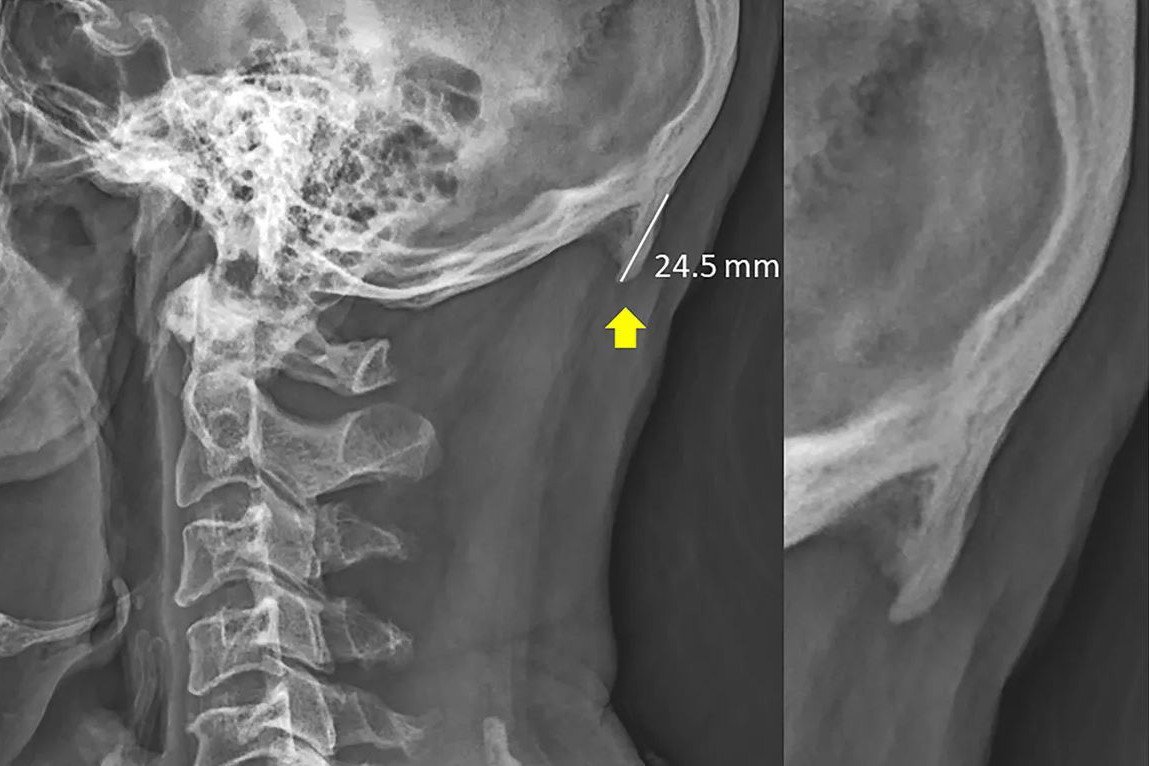

Самый точный вариант - это рентген.

Размер новой кости достигает 3 см. Доктор Шахар говорит, что отростки никогда не исчезнут. Они будут становиться все больше и больше.